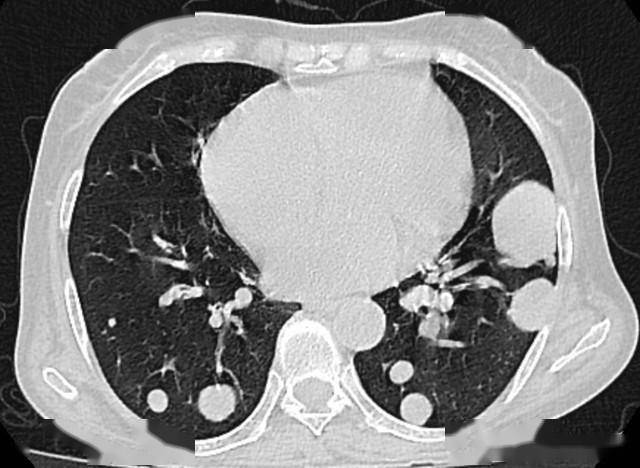

2. 肺结节:90%以上是良性

随着低剂量螺旋CT的普及,肺结节检出率越来越高,但恶变概率大多在10%以内。需要警惕的是这两类:

- 大小:直径超过8mm的结节,尤其是磨玻璃结节,要缩短复查间隔(3-6个月一次);

- 形态:结节边缘不清晰、密度不均,或短期内明显增大,需要进一步检查排除肺癌风险;

- 提醒:长期吸烟、有肺癌家族史的人,即使结节小,也建议定期随访。